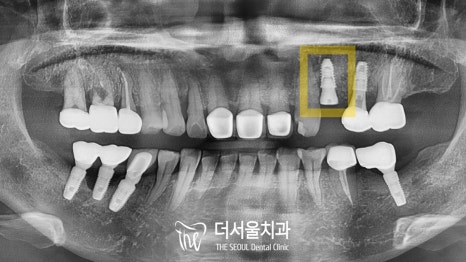

엑스레이 촬영을 통해 확인했더니

역시나 염증으로 인해 치조골 소실이 나타났네요.

표시해둔 곳을 보면 검게 변해 있는 것을 볼 수 있습니다.

더는 자연치를 살리기에는

무리가 있다는 판단이 들었는데요.

따라서 더서울에서는

디지털 임플란트를 통해

개선하는 것으로 방향을 잡았습니다.